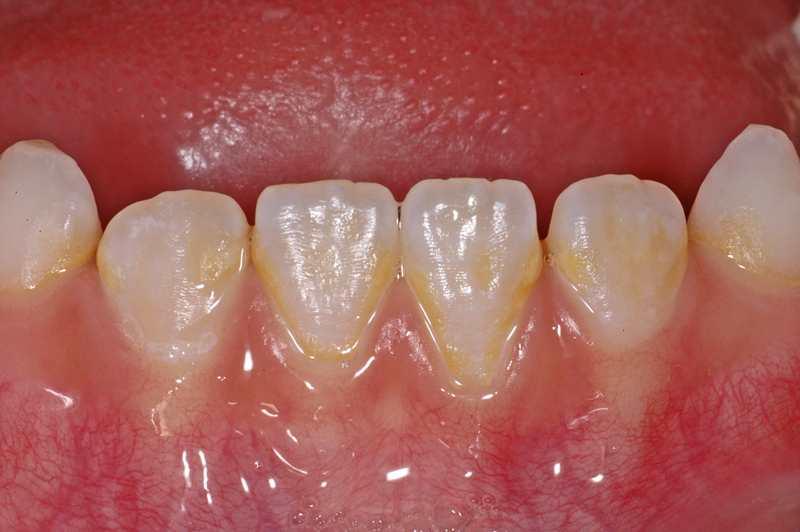

Hier ein weiterer Fall mit weissen / gelblichen Flecken an einem unteren linken mittleren Schneidezahn (Zahn 31). Diese Flecken gehen gegen den Zahnfleischrand ins Gelbliche über. Die grossflächigen Flecken auf der Zahnaussenseite sind durch eine Zahnschmelzbildungs-Variation bedingt und «im Zahn drin».

Zudem hat der Zahn 31, wie die anderen auch, braune Auflagerungen im Bereich der Zahnzwischenräume. Diese Verfärbungen lassen sich in der Regel gut reinigen und entfernen.

Ebenfalls gut sichtbar auch hier die Perikymatien (die Querrillen).

- Weisser / gelblicher Fleck an einem 31